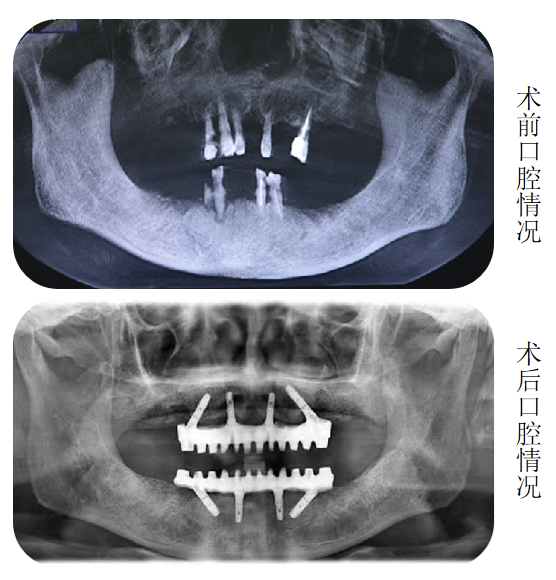

“这个您不用担心。”海涛口腔种植科唐主任经过口内数据分析和会诊后告诉李大妈:“我们借助计算机,设计出您口腔内8个适合种植的位置,利用海涛“一天得”全口种植牙技术,上下半口各4颗种植体就能分别完成半口牙修复,恢复全口咀嚼功能。”

更少的种植体+无需植骨+精准的力学设计,当天种出一口新牙

海涛口腔唐主任介绍,海涛“一天得”全口种植牙是海涛口腔的特色技术,数字化导航定位,植入精准,只需植入4颗或6颗种植体就可以解决半口无牙问题,并且当天种牙,当天就可戴牙吃饭。整个手术过程一次性完成,大大缩短了患者的就诊时间和次数,节省了治疗费用,价格相比传统种植牙省了很多。同时,该技术采用2毫米的钛丝,结合国际先进的口内冷焊接技术焊接而成,稳定性非常好。与此同时,该技术打破传统种植技术瓶颈,破解牙槽骨萎缩、骨量不足等种植难题,无需植骨不增加额外费用,让这一缺牙群体也能实现种植牙。